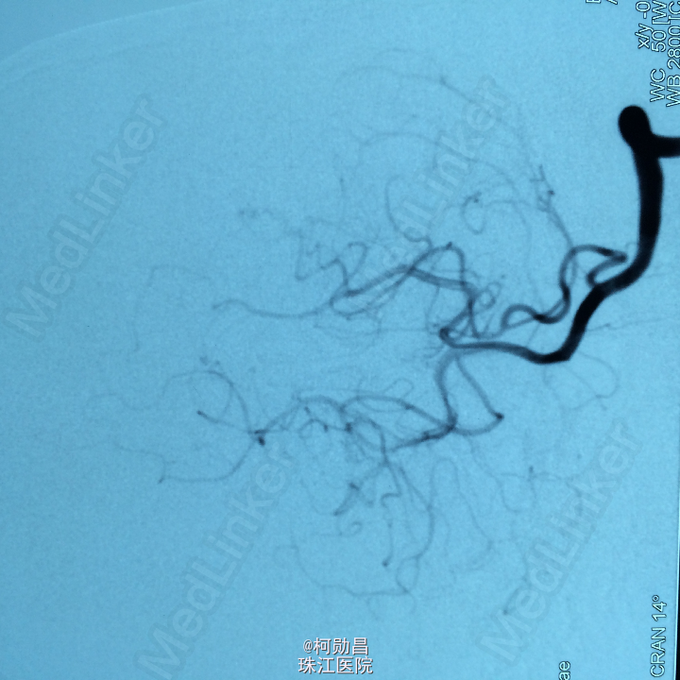

诊断:左侧顶叶占位 处理:行DSA检查,提示肿瘤染色,予PVA颗粒行血管内栓塞治疗。

术后再予开颅手术治疗,书中见供血动脉闭塞,出血量少。